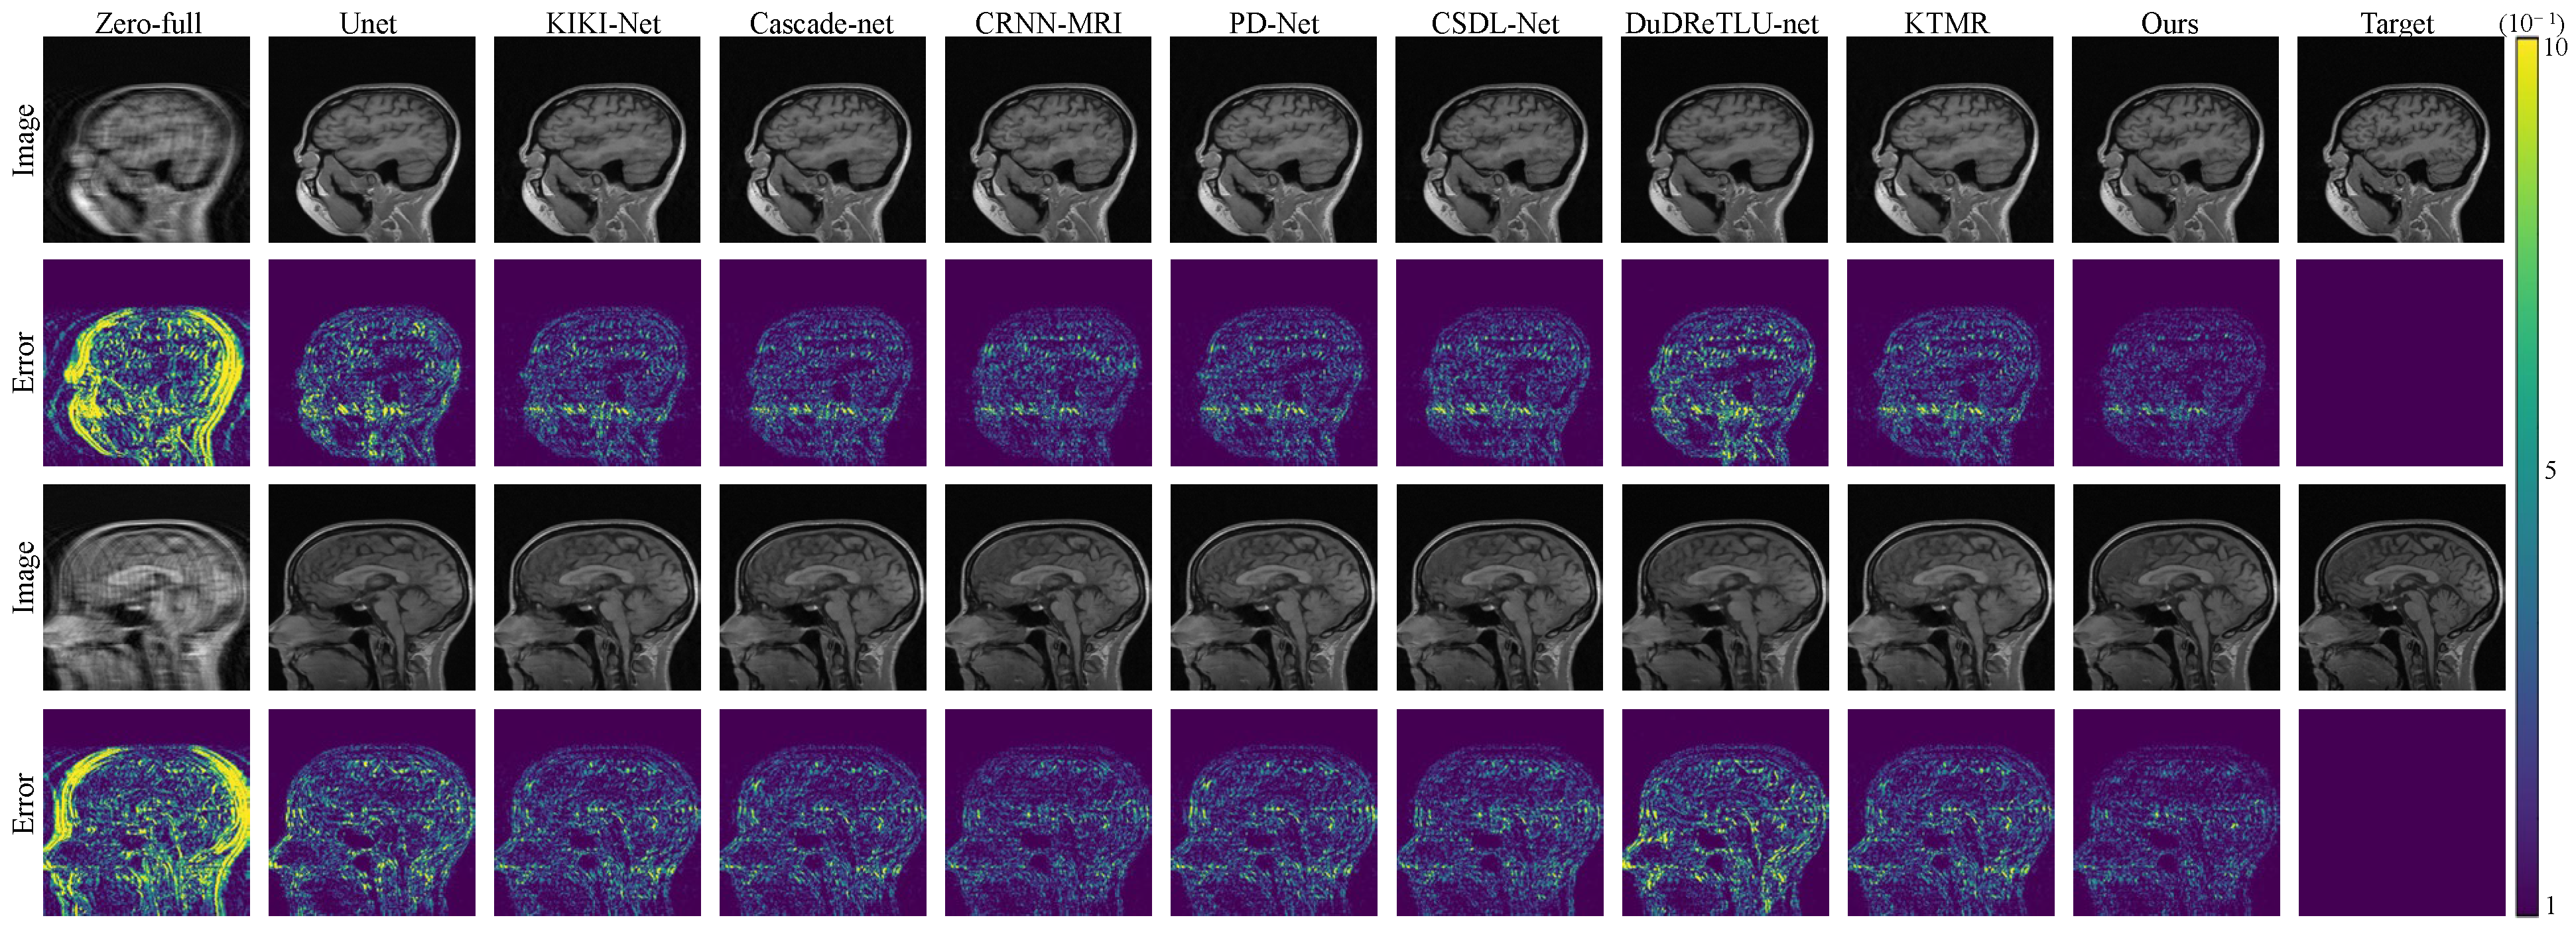

As shown in Figure 4 and Figure 5, both in the error maps and the reconstructed images, our algorithm demonstrates smaller errors and more accurate texture structures, which is similar to the results observed in the FastMRI dataset.

Figure 5. The reconstruction results and error maps are compared among 8 algorithms under 8× acceleration on the Calgary-Campinas dataset.

Electronics 12 04742 g005